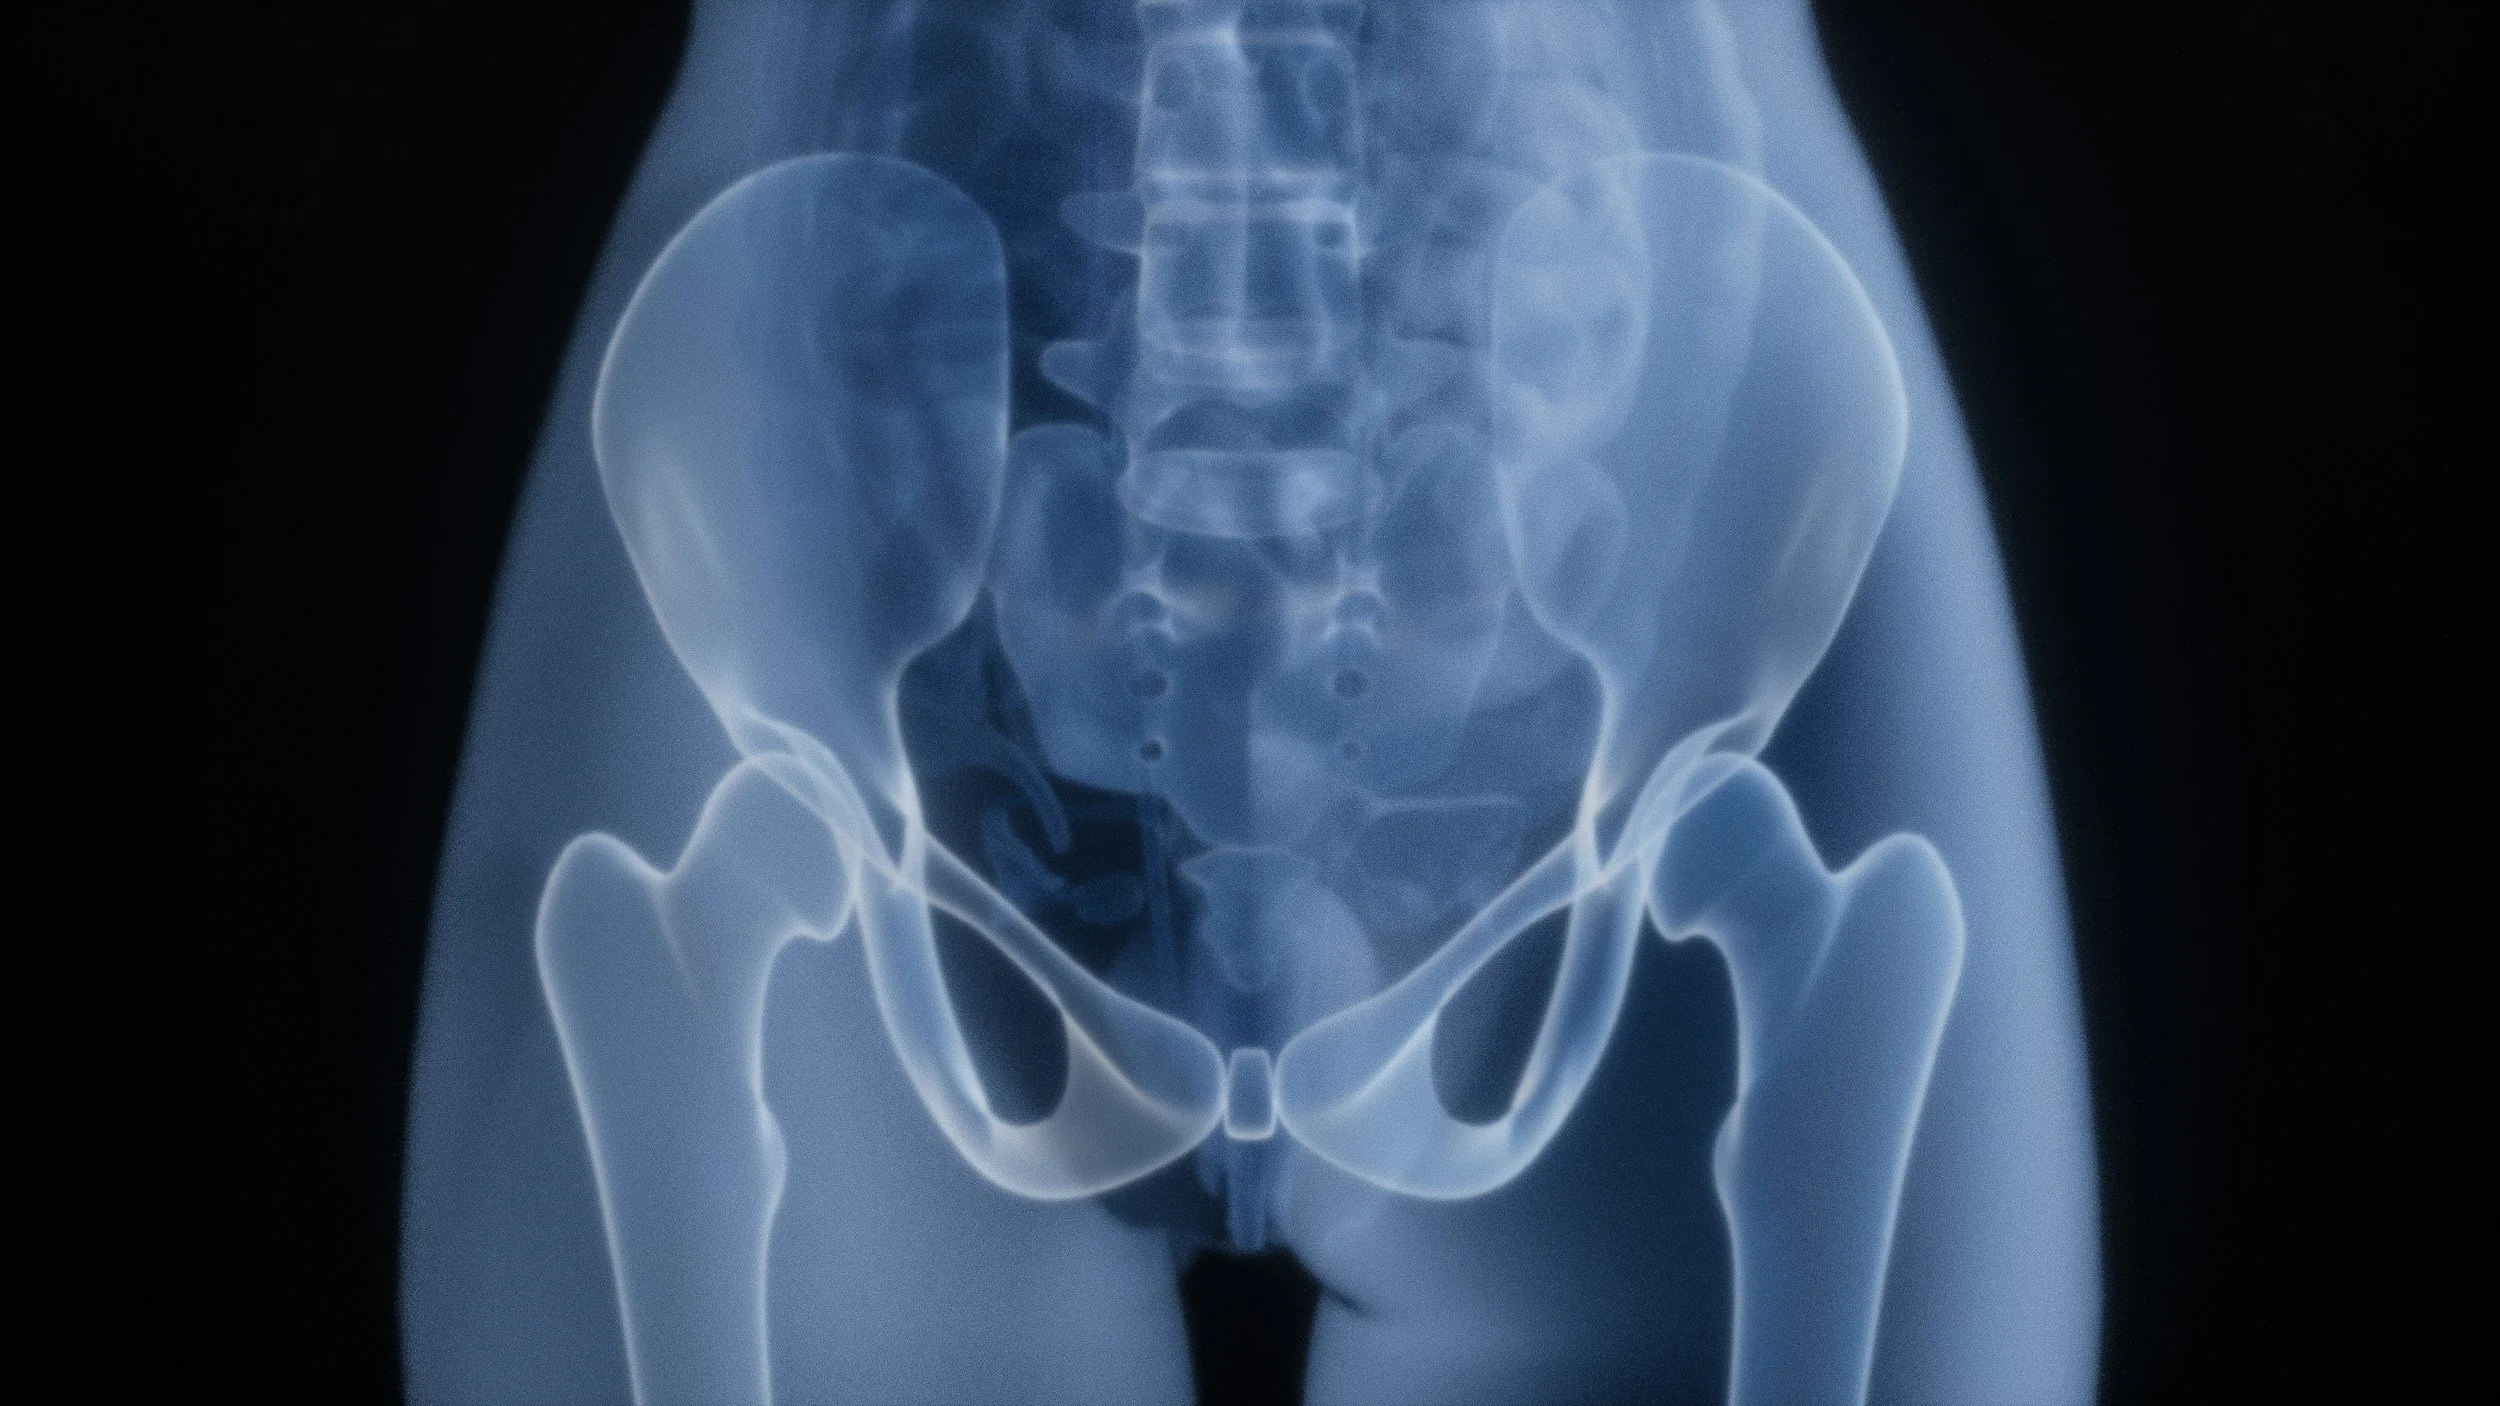

Understanding Your Bones: Why Testing Matters

As we get older, bone loss can happen quietly. There’s often no pain, no warning signs—until something like a fracture occurs. That’s why testing is so important.

Many people are familiar with the traditional DEXA scan, but there’s a newer option gaining attention called a REMS scan (Radiofrequency Echographic Multi Spectrometry). What makes it especially appealing is that it uses ultrasound technology rather than radiation, making it a comfortable and repeatable way to monitor bone health over time.